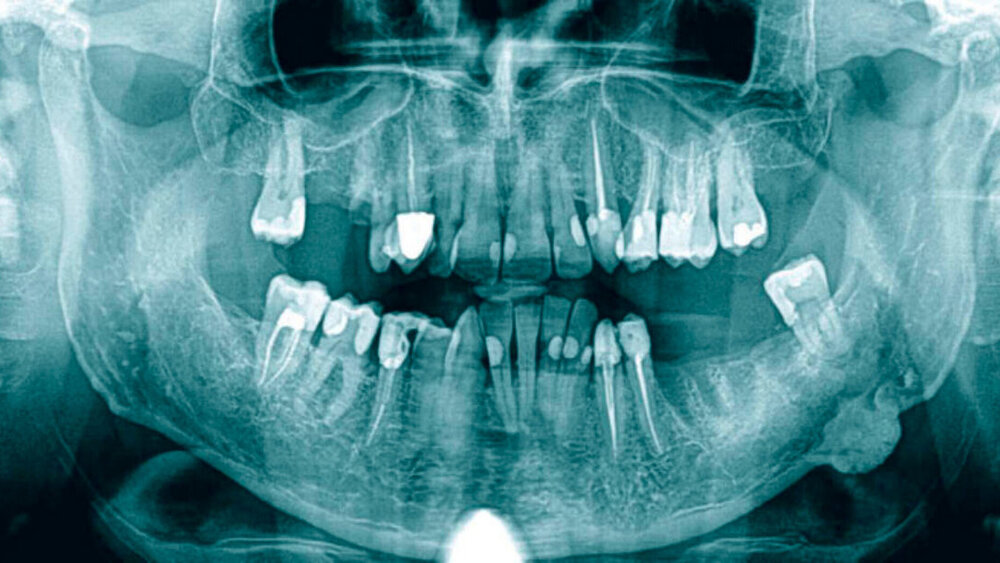

In der Bildgebung war eine am Unterrand des Unterkieferkorpusbereichs übergangslos angelagerte, halbkugelig anmutende Struktur mit scharfer Begrenzung sichtbar. Die Binnenstruktur zeigte sich vorwiegend radioopak mit wenig transluzenten Anteilen ohne eindeutiges Grundmuster (Abbildung 1). Klinisch präsentierte sich ein gesunder Mann im stabilen Allgemeinzustand ohne körperliche Beschwerden. Vorerkrankungen, Traumata, eine Dauermedikation oder in der Vergangenheit stattgehabte Operationen lagen anamnestisch nicht vor. Verlaufsröntgenbilder waren nicht vorhanden.

Periphere Osteome präsentieren sich als gut abgrenzbare, ovaläre radioopake Läsion mit Basis an der Kortikalis [Hernando et al., 2018], die kortikale Assoziation fehlt bei zentralen oder extraossären Osteomen. Differenzialdiagnostisch sollten ein maligner Tumor oder andere Tumore des ossifizierenden Formenkreises ausgeschlossen werden [Starch-Jensen, 2017], wobei eine sichere Zuordnung nur über eine histopathologische Untersuchung möglich ist. Bei Unklarheiten sollte daher eine Entfernung im Sinne einer Exzisionsbiopsie erfolgen. Bei vollständiger Entfernung eines Osteoms sind Rezidive höchst selten [Starch-Jensen, 2017; Hernando et al., 2018] und eine maligne Transformation wird nicht beschrieben [Starch-Jensen, 2017].